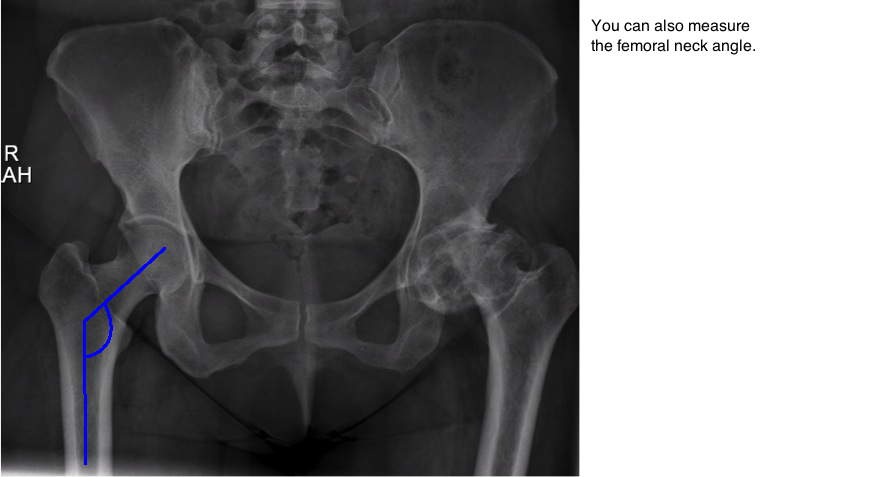

measure femoral neck angle on ap pelvis